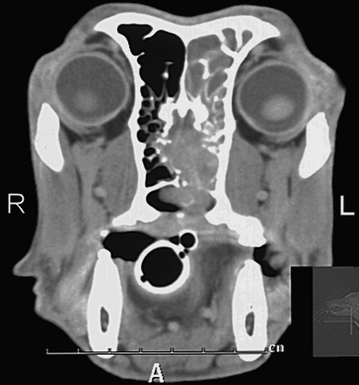

How Long Can A Dog Live With Metastatic Cancer - Metastasis Archives Dog Cancer Blog : One interesting thing, however, is that the tumor numbers or location don't seem to influence the survival rate.. Computed tomography (ct scan) can be performed to identify some of these lung tumors. Because spread to the lung occurs late in the clinical course of a malignant tumor, the outlook is poor. Response rates to chemotherapy are not well documented as there are not many that have been performed. The life expectancy of a dog diagnosed with lung cancer can be up to 22 months, depending on the type of tumor and on the treatment the dog undergoes. This information was relayed to both owners, including expected quality of life, both with and without treatment.